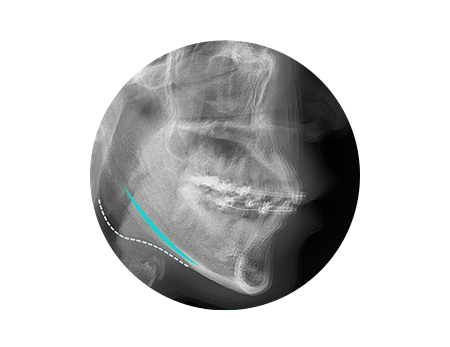

광대축소 수술방법

아이디병원에서는 3D-CT를 활용해

안면신경의 손상을 피하여 최적의 효과를 위한

절골량과 절골의 위치를 결정합니다

사선 절골 방식으로 더 많은 양의 광대뼈를

후측방으로 이동시켜 어느 각도에서나

확실한 효과를 보여드립니다